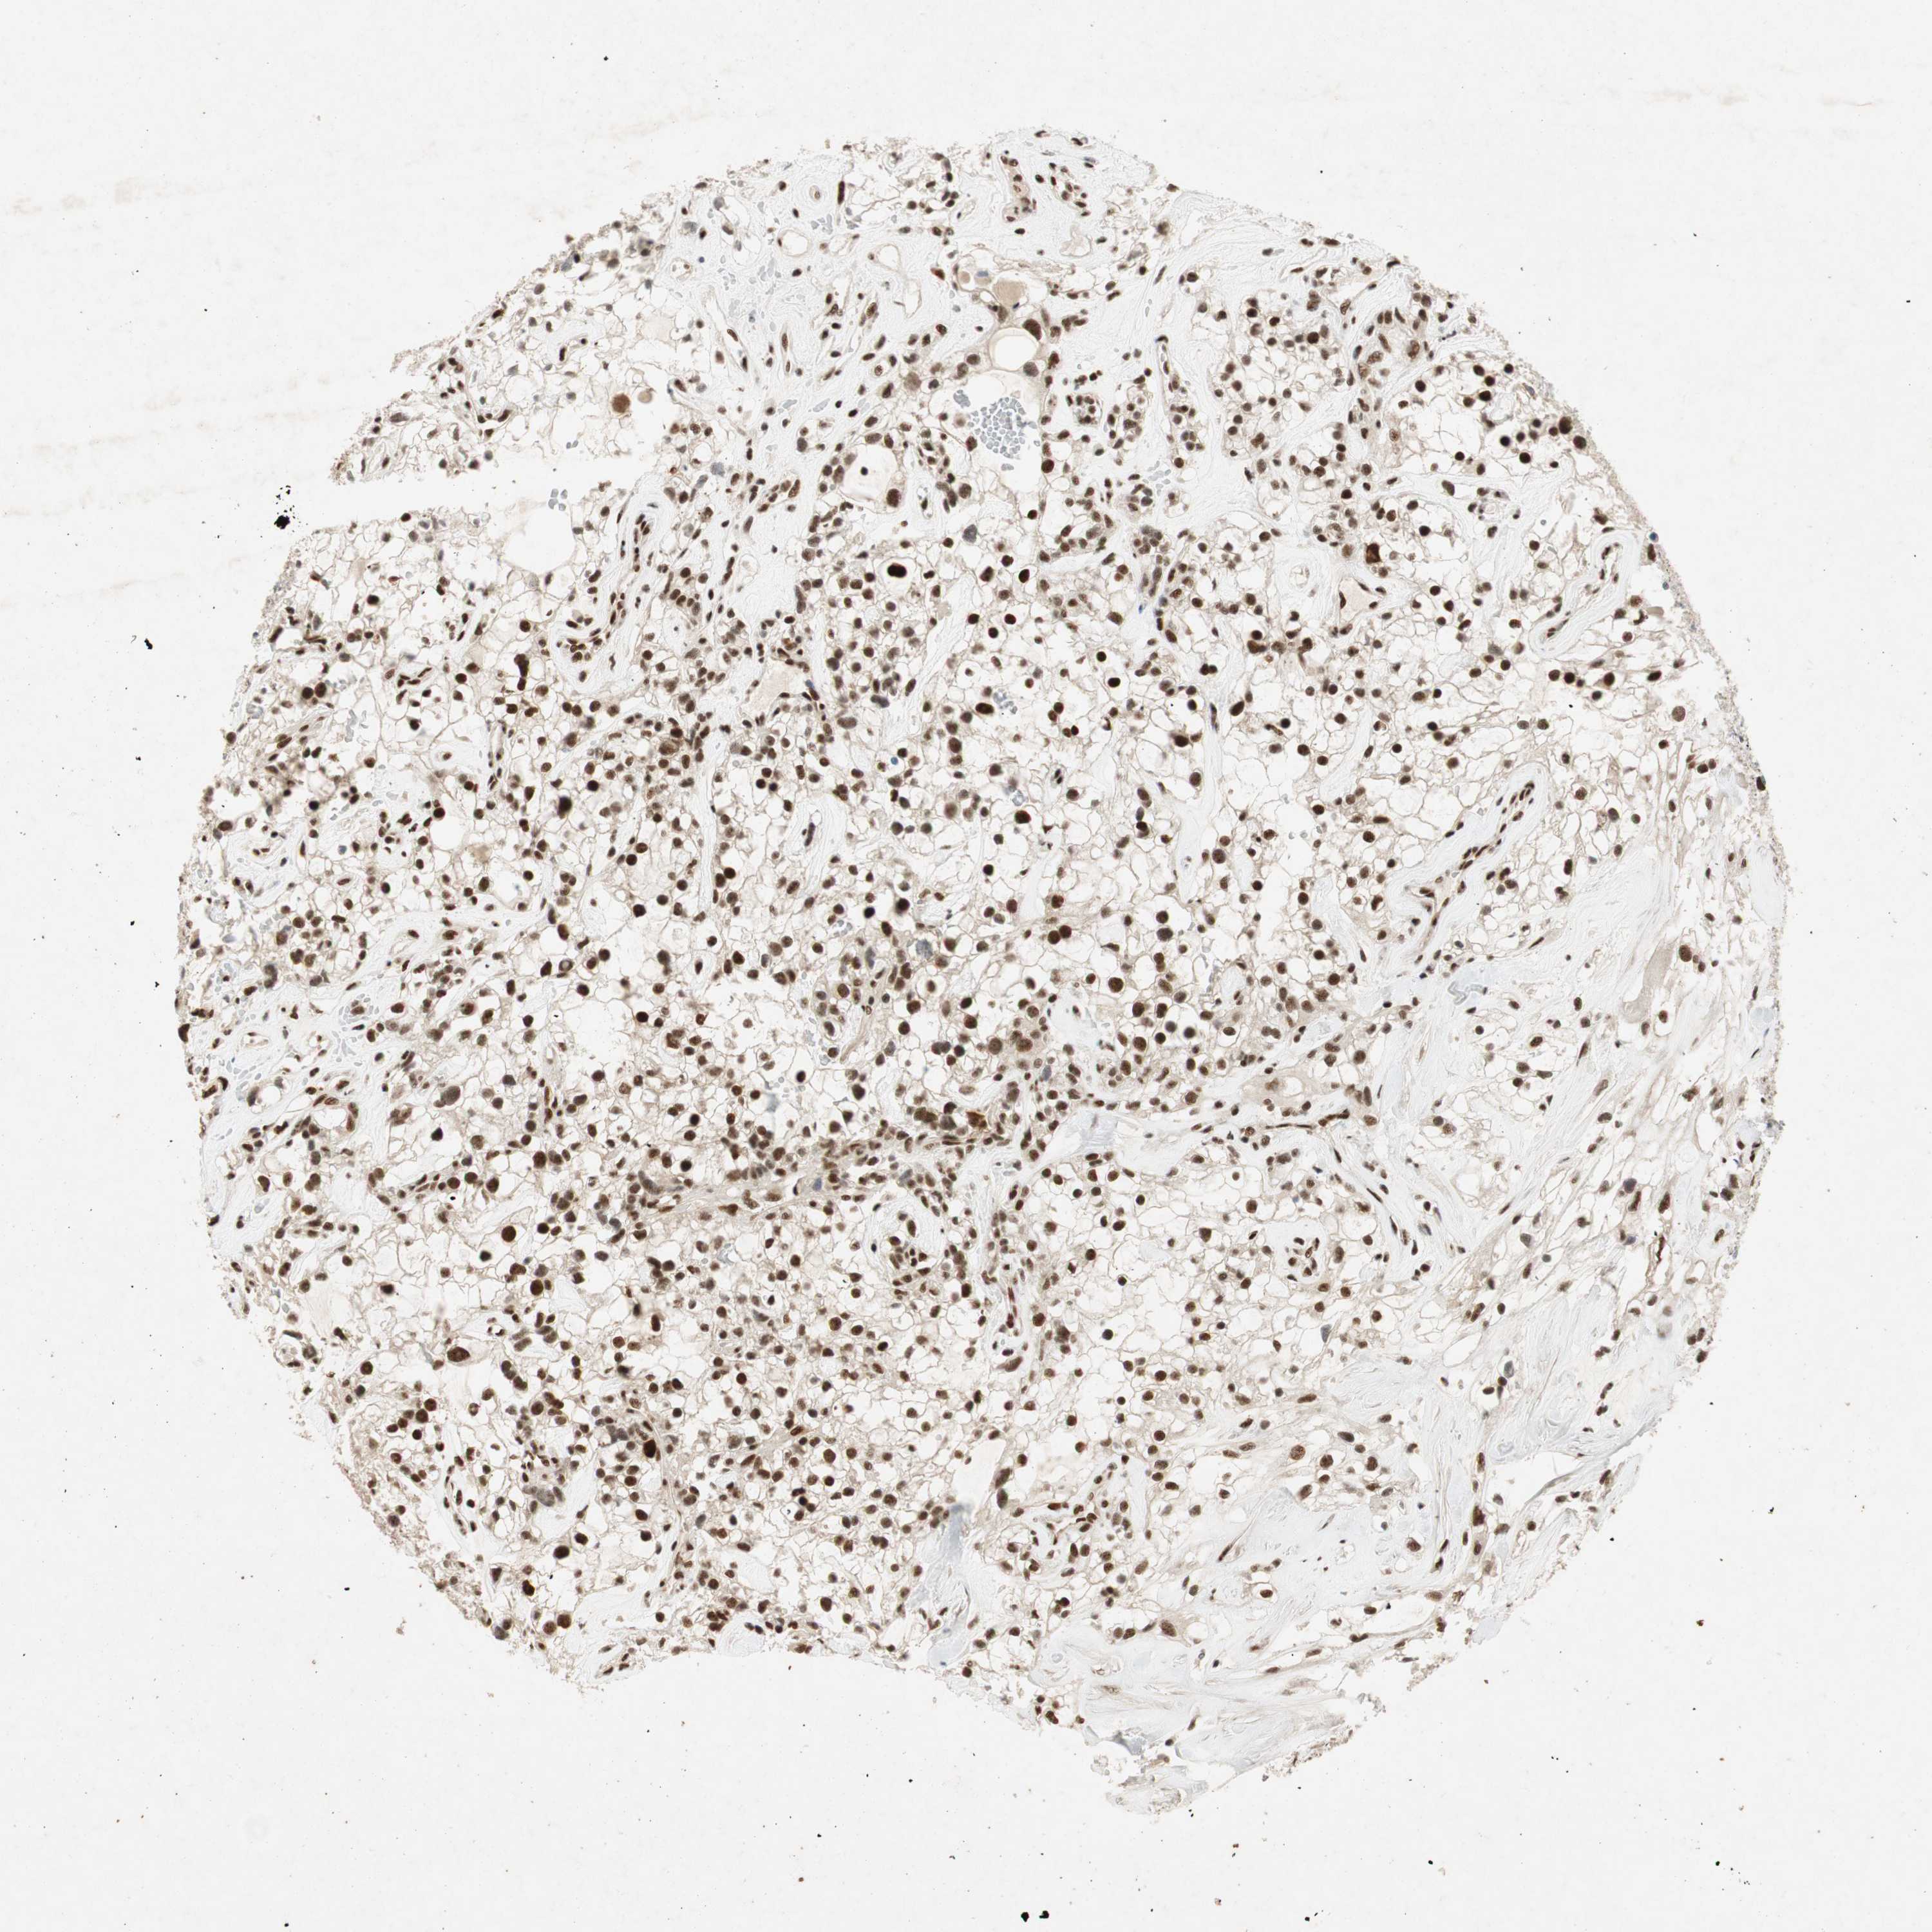

KIDNEY RENAL CLEAR CELL CARCINOMA (VALIDATION) - Interactive survival scatter ploti

The Survival Scatter plot shows the clinical status (i.e. dead or alive) for all individuals in the patient cohort, based on the same data that underlies the corresponding Kaplan-Meier plots. Patients that are alive at last time for follow-up are shown in blue and patients who have died during the study are shown in red.

The x-axis shows the expression levels (FPKM) of the investigated gene in the tumor tissue at the time of diagnosis. The y-axis shows the follow-up time after diagnosis (years). Both axes are complimented with kernel density curves demonstrating the data density over the axes. The top density plot shows the expression levels (FPKM) distribution among dead (red) and alive patients (blue). The right density plot shows the data density of the survived years of dead patients with high and low expression levels respectively, stratified using the cutoff indicated by the vertical dashed line through the Survival Scatter plot. This cutoff is automatically defined based on the FPKM cutoff that minimizes the p-score. The cutoff can be changed by dragging the vertical line or by entering a cutoff value in the square labeled "Current cut-off".

Under the Survival Scatter plot the p-score landscape (black curve; left axis) is shown together with dead median separation (red curve; right axis). Dead median separation is the difference in median mRNA expression between patients who have died with high and low expression, respectively. It is calculated as follows: median FPKM expression of dead patients with high expression - median FPKM expression of dead patients with low expression. This is intended to aid the user in visually exploring custom cutoffs and the associated p-scores and dead median separation.

Individual patient data is displayed and can be filtered by clicking on one or more of the category buttons on the top of the page. Categories describing expression level and patient information include: high, low, alive, dead, female, male and tumor stages. The scale of the x-axis can be toggled between linear and log-scale by clicking on the "x log" button. Mouse-over function shows TCGA ID, patient information and mRNA expression (FPKM) for each patient.

& Survival analysisi

Kaplan-Meier plots summarize results from analysis of correlation between mRNA expression level and patient survival. Patients were divided based on level of expression into one of the two groups "low" (under cut off) or "high" (over cut off). X-axis shows time for survival (years) and y-axis shows the probability of survival, where 1.0 corresponds to 100 percent.

NCBP3 is not prognostic in Kidney Renal Clear Cell Carcinoma (validation)

Best expression cut offi

Based on the FPKM value of each gene, patients were classified into two groups and association between prognosis (survival) and gene expression (FPKM) was examined. The best expression cut-off refers the FPKM value that yields maximal difference with regard to survival between the two groups at the lowest log-rank P-value. Best expression cut-off was selected based on survival analysis .

When clicking on this number, the vertical dashed line indicating cut-off, the interactive survival plot, and the Kaplan-Meier curve will be adjusted to show results based on the best expression cut-off.

: 7.56

P scorei

Log-rank P value for Kaplan-Meier plot showing results from analysis of correlation between mRNA expression level and patient survival.

N/A

TCGA RNA samplesi

RNA-seq data is reported as average FPKM (number Fragments Per Kilobase of exon per Million reads), generated by the The Cancer Genome Atlas (TCGA) .

Normal distribution across the dataset is visualized with box plots, shown as median and 25th and 75th percentiles. Points are displayed as outliers if they are above or below 1.5 times the interquartile range. FPKM values of the individual samples are presented next to the box plot.

Average pTPM 8.6

Number of samples 100